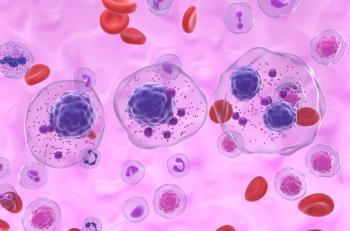

Updated results from a phase 1 study showed that KLN-1010 produced reduced MRD-negative responses in all treated patients with RRMM.